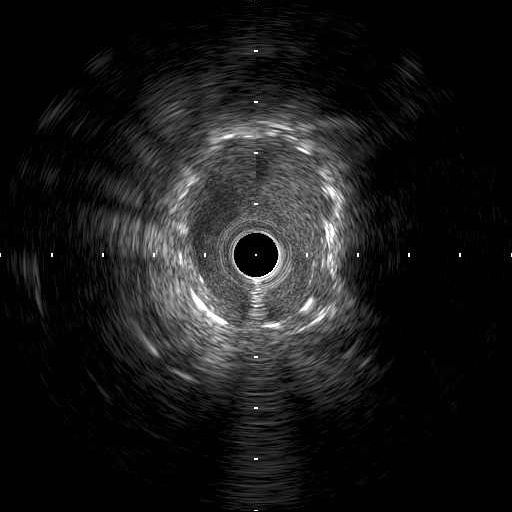

We used 7Fr JR3.5SH guiding and SION blue ES wire. Wire was easily crossed, and IVUS showed in-stent restenosis with neointimal hyperplasia and underexpanded stent. Long inflation technique using cutting balloon was performed, and Biolimus-A9 coated stent was deployed for in-stent lesion. Post dilation using NC balloon was performed, and procedure was completed. 4 months and 1year and 9 months after the procedure, follow up CAG with coronary angioscopy was performed.

1 year and 2 months after the initial procedure using underexpanded stent for eccentric calcified plaque placed at RCA ostium, in-stent restenosis was occurred. PCI was performed with drug-coated balloon and another 8 months later, re-restenosis was occurred. PCI was performed again with Biolimus-A9 coated stent deployed for in-stent lesion. 4 months, and 1 year and 9 months after the stent implantation, CAG was performed with evaluating coronary angioscopy. At the 4 months later, there was no restenosis and we confirmed beginning of neointima coverage for stent strut. At the 1 year and 9 months later, there was also no restenosis, and we confirmed enough and optimal neointimal coverage as vessel healing after stent implantation. Biolimus-A9 coated stent has early drug release system and polymer-free characteristics. The characteristics of the stent may have contributed to get the early smooth and optimal neointimal coverage, and the prevention of malignant cycle of RCA ostium in-stent restenosis.